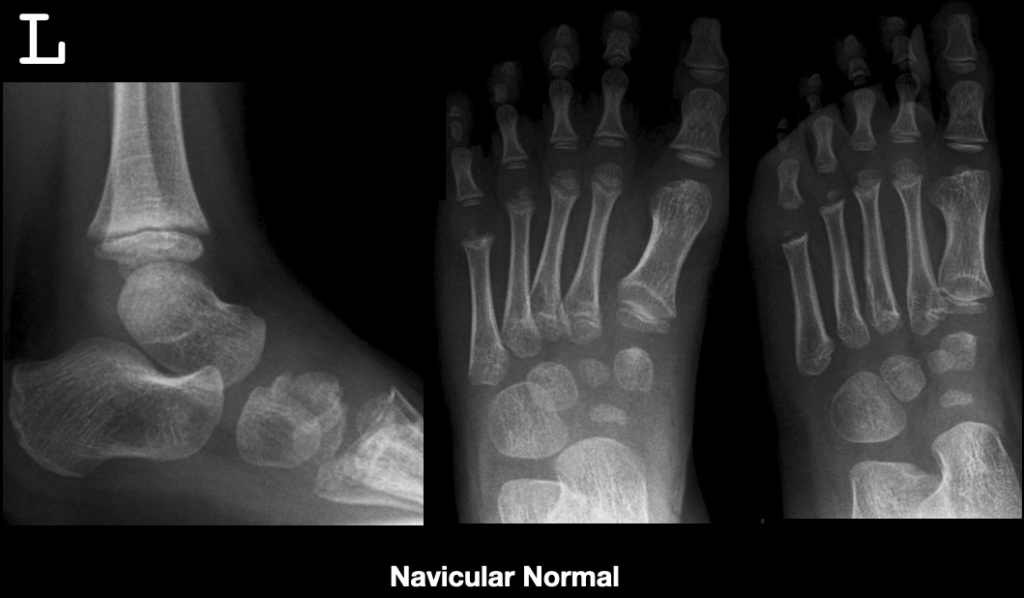

Kohler Disorder General Discussion Kohler disorder is a remarkable Kohler's Disease Child It causes inflammation of an outgrowth to the tarsal. Kohler's disease is a rare idiopathic condition caused by avascular necrosis of the navicular bone that occurs in young children. The foot becomes swollen and painful, and the arch of the foot. Köhler bone disease usually affects children aged 3 to 5 years (more commonly boys) and typically affects only one. Kohler's Disease Child.